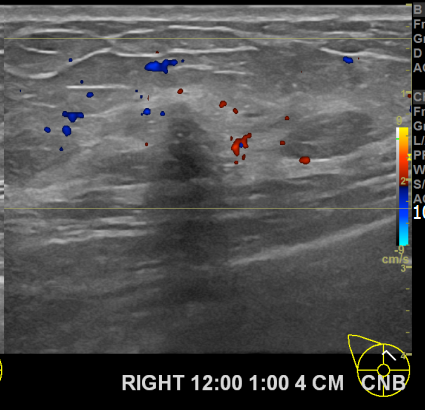

상기환자 외부검사이상으로  우측조직검사를위해  내원하신 60대후반 여성분으로

우측 조직검사 시행해 침윤성암으로 진단되었습니다